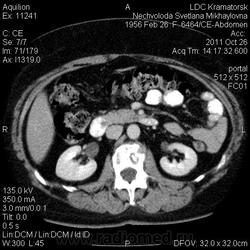

Здравствуйте! Вот уже месяц не могут поставить диагноз. Первичный очаг найти не удалось. Множественная миелома (несекретирующая?, т.к. по крови стерн. пункция не дает результата)?

Костное окно:

По имеющимся файлам-дайком я не нашла признаков опухоли. Имеется множественное остеолитическое поражение позвоночника, ребер, грудины, частично - таза. Лимфоузлы не увеличены. Тоже поставила бы на первое место миеломную болезнь. Диагностирование её не всегда простое дело. Поражена грудина и, наверное, нужно посоветоваться с онкологом (гематологом) стоит ли сделать стернальную пункцию.Советую написать в личку tatyana.